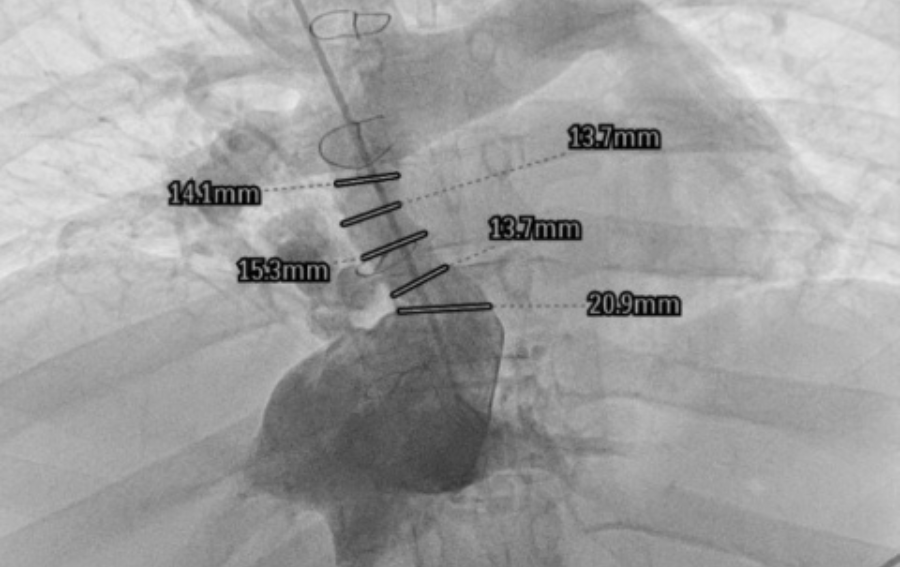

U pacjentki wszczepiony chirurgicznie konduit (przewód) doprowadzający krew z żyły głównej dolnej do łożyska płucnego uległ istotnemu zwężeniu. Kardiolodzy interwencyjni z dostępu przez żyłę główną górną (obie żyły udowe były niedrożne) poszerzyli ten konduit stentgraftem z bardzo dobrym efektem.